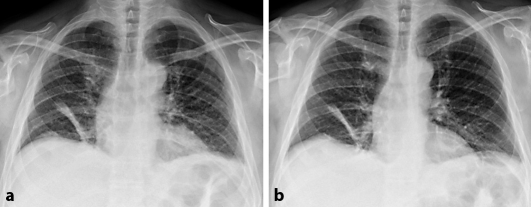

A chest CT and a whole-body positron emission tomography-CT showed no evidence of malignancy or inflammation. An X-ray cinematography of the chest revealed an elevated diaphragm with only marginal movement during inspiration (fig. 1). Videolaryngoscopic examination showed signs of partial paralysis of both branches of the vagus nerves, namely both the recurrent laryngeal nerves and the superior laryngeal nerves. The excavated vocal folds were in an intermediate position, with minimal non-intended adduction movements. The muscle tension of the ventricular folds was decreased (fig. 2).

Fig. 1.

Chest X-ray at initial visit in maximum expiration (a) and maximum inspiration (b), showing paresis of the diaphragm and partial atelectasis of the right lung.

At reassessment after 2 months, phonation had markedly improved, but hoarseness was still present. Further neurological examination remained unchanged, except for a mild atrophy of the right supraspinatus muscle. During videolaryngoscopy, the excavated vocal cords were mobile; however, during phonation, glottal closure was still insufficient over the whole length of the glottis. While the gap between the processus vocales was closely to 1 mm, it was approximately 2 mm between the excavated vocal folds in the mid of the glottis (fig. 2). Tension of the ventricular folds returned to normal. Results of the EMG, phrenic nerve conduction velocity, lumbar puncture and spirometry were unaltered. A chest X-ray revealed an unchanged elevation of the diaphragm, with restricted mobility during inspiration.

The typical course of NA is initiated by a distinct pain in the shoulder, followed by muscle weakness and atrophy. However, NA involving other peripheral nerves or isolated affection of single motor nerves can be difficult to diagnose. In our case, acute-onset dyspnea and orthopnea were the predominant symptoms suggestive of a cardiac etiology or bronchial asthma. The rapidly progressive hoarseness, leading to aphonia within 48 h and worsening of dyspnea when lying flat, was indicative for an atypical NA [3, 7, 12]. A decrease in the forced vital capacity of more than 40% in the standing compared to the supine position is suspicious of diaphragmatic paresis; therefore, the forced vital capacity should be assessed in both positions, if possible. Phrenic nerve conduction velocity can be prolonged or, as in our case, normal [5]. The EMG of the diaphragm could have helped to confirm the diagnosis of diaphragmatic paralysis [3, 13], but was not performed in our case due to the associated relatively high risk of pneumothorax. The chest X-ray revealed an elevated diaphragm on both sides with nearly no movement during inspiration, and the maximum inspiratory pressure was severely reduced.